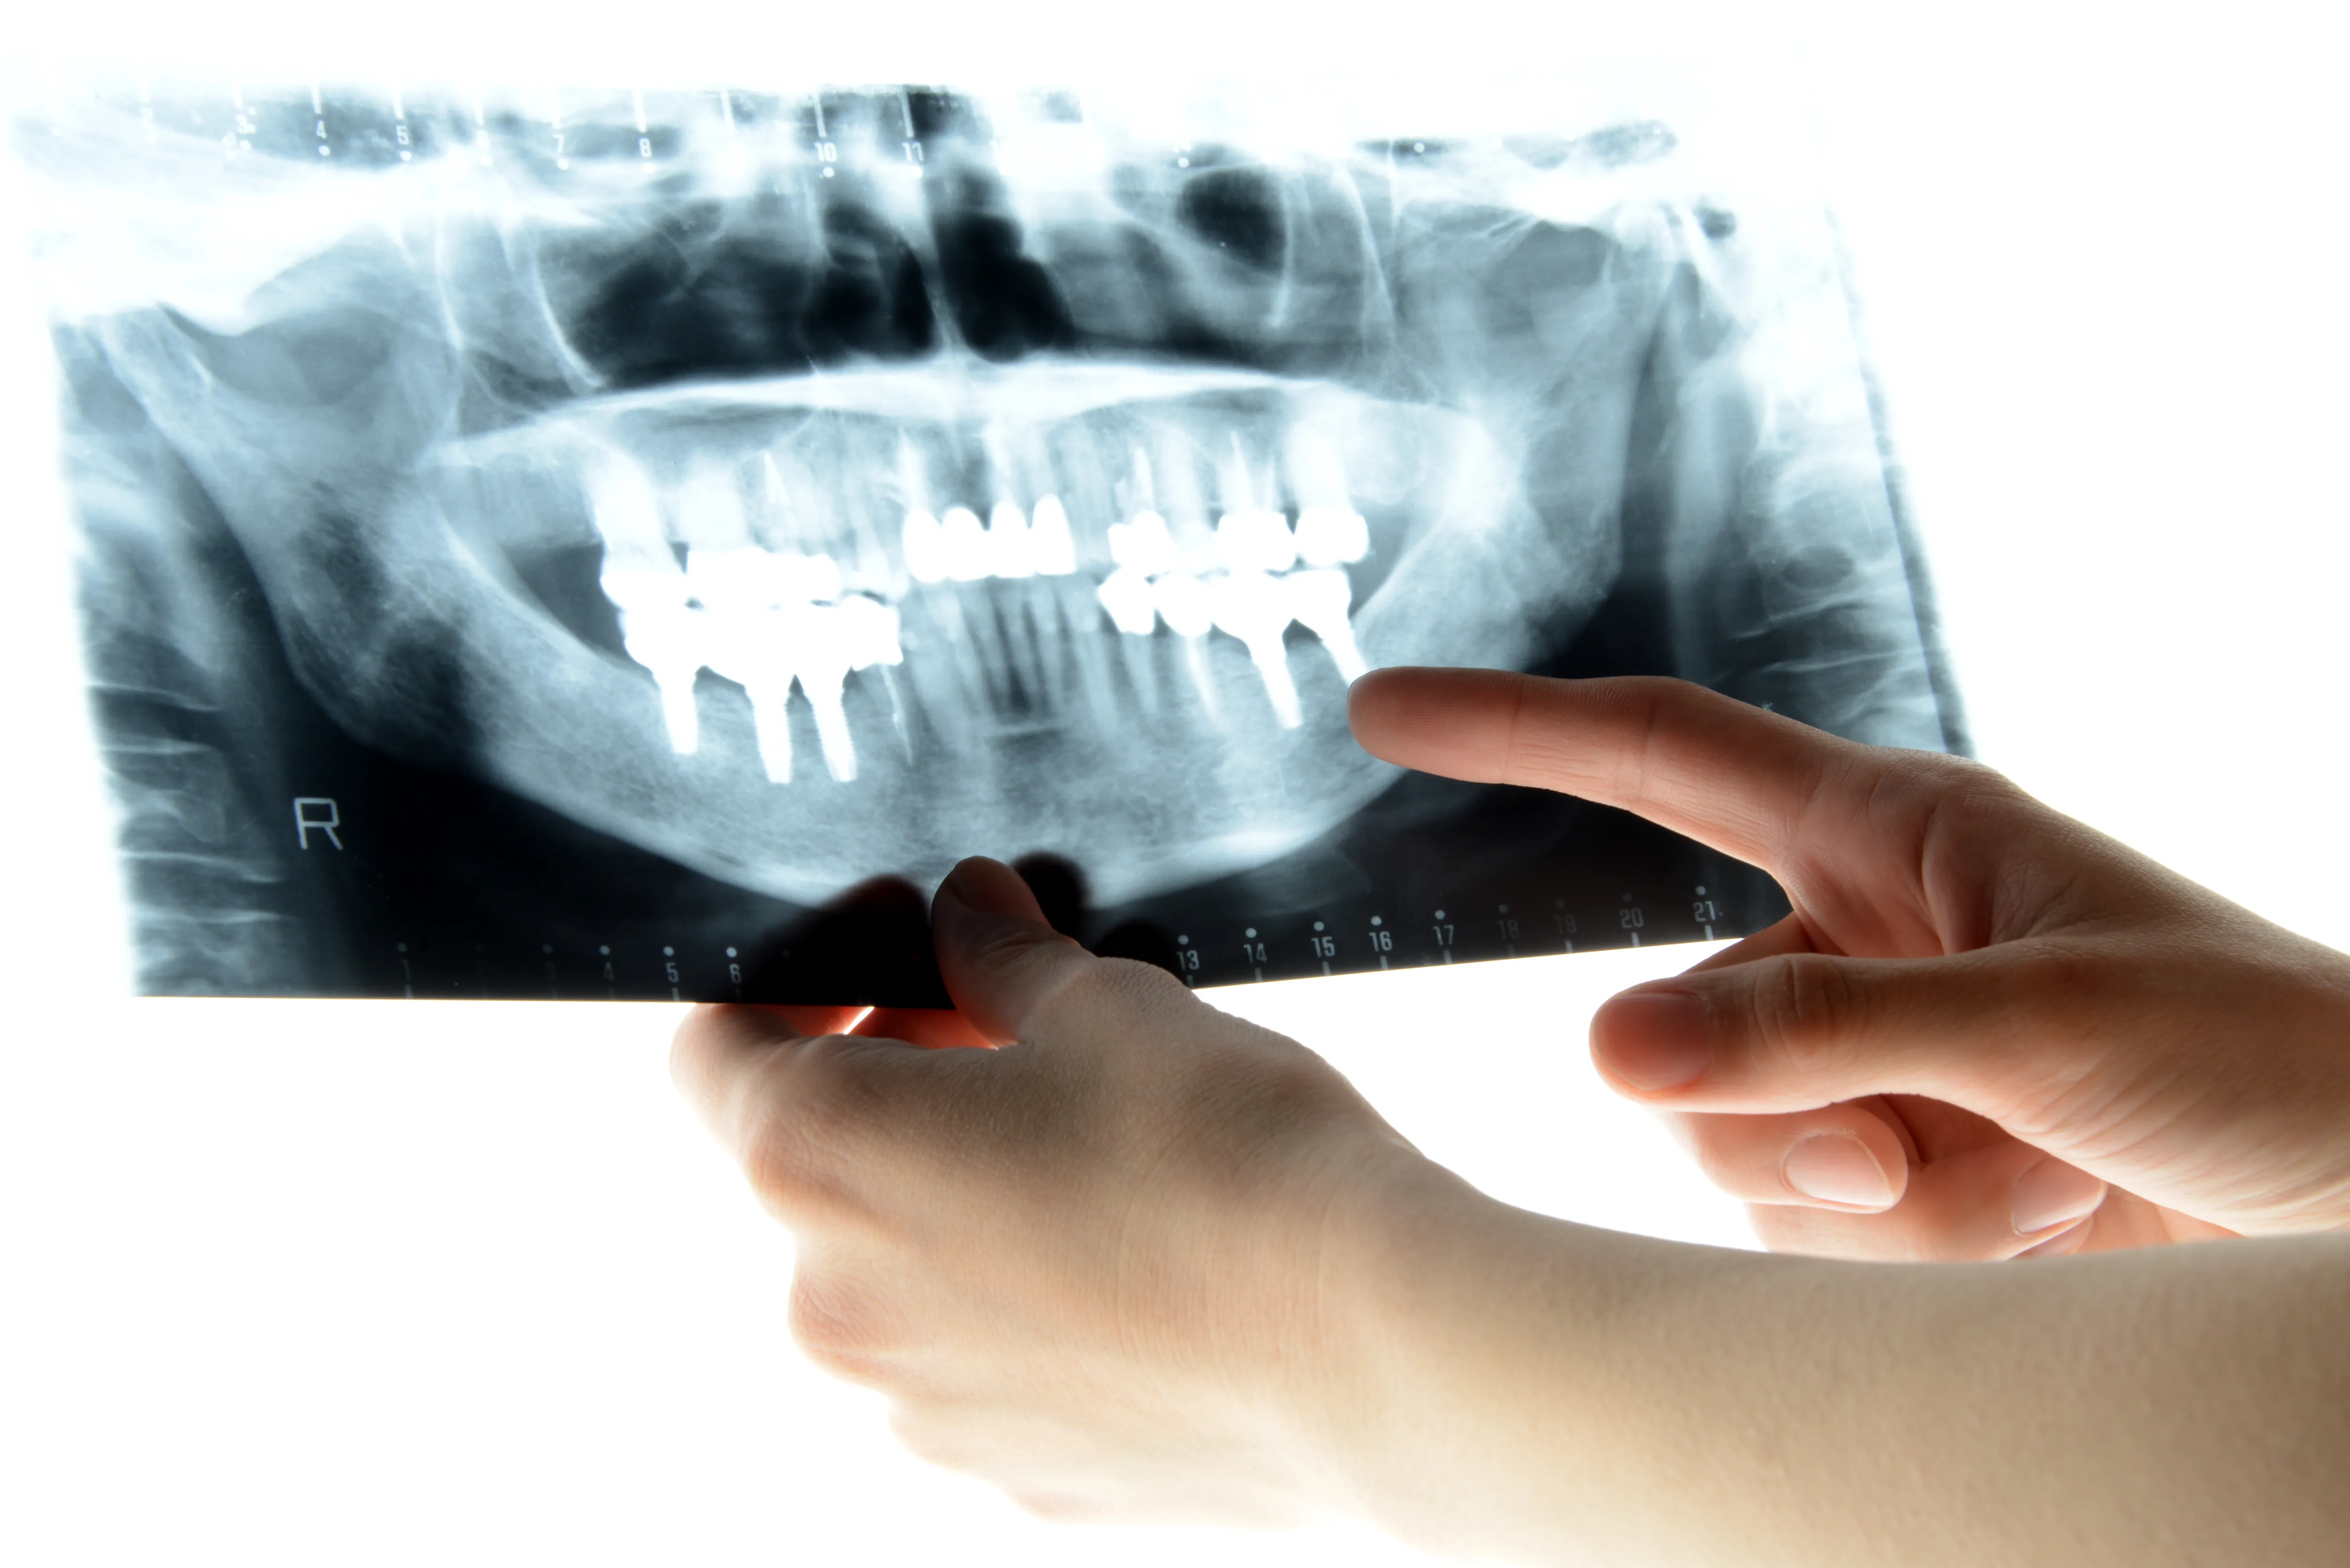

顎関節症の診断には、専門的な知識と経験が必要です。当院には口腔外科の専門知識を持つ医師が在籍しており、詳しい問診、触診、画像検査により、正確な診断を行います。

顎の動きを観察し、関節の音や筋肉の緊張度を確認します。レントゲンやCT撮影により、関節の骨の状態や変形の有無も確認できます。

顎の動きを観察し、関節を触診します。口を開け閉めする際の音や動き、最大開口量(どのくらい口が開くか)を測定します。レントゲンやCT撮影により、関節の骨の状態を確認します。

検査結果をもとに、顎関節症のタイプを診断します。画像をご覧いただきながら、現在の状態と治療方針をわかりやすくご説明します。